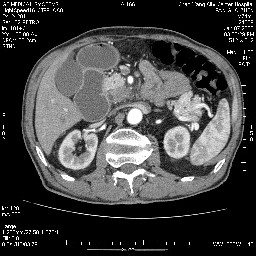

女,74岁,呕吐10余日

壶腹部的占位性病变,考虑为十二指肠癌并梗阻,但脾内多发性低密度区为转移吗?

还有胃、脾之间可见有侧支循环建立。左肾盂积水。

考虑来源于十二指肠水平段的恶性占位,侵及周围组织,特别是胰腺,可见区域淋巴结肿大,左侧下腔静脉畸形。

十二指肠水平段腔内占位伴梗阻,中等度较为均匀的强化,洗脱慢,区域淋巴结显示增多,符合腺癌表现。下腔静脉变异。

十二指肠降段扩张,水平段狭窄成鼠尾状,肠壁明显增厚,胰腺勾突增大成不均匀强化,其内可见低密度区,胆囊增大,1十二指肠水平段腺癌侵犯胰腺勾突可能大,2胰腺癌侵犯十二指肠(只有胆囊增大没有肝内外胆管扩张不好解释)代除外.

十二指肠降段扩张,水平段狭窄成鼠尾状,肠壁明显增厚,胰腺勾突增大成不均匀强化,其内可见低密度区,胆囊增大,1十二指肠水平段腺癌侵犯胰腺勾突可能大,2胰腺癌侵犯十二指肠 。

今日手术结果:胰腺钩突癌侵犯十二直肠,腹腔淋巴结转移.